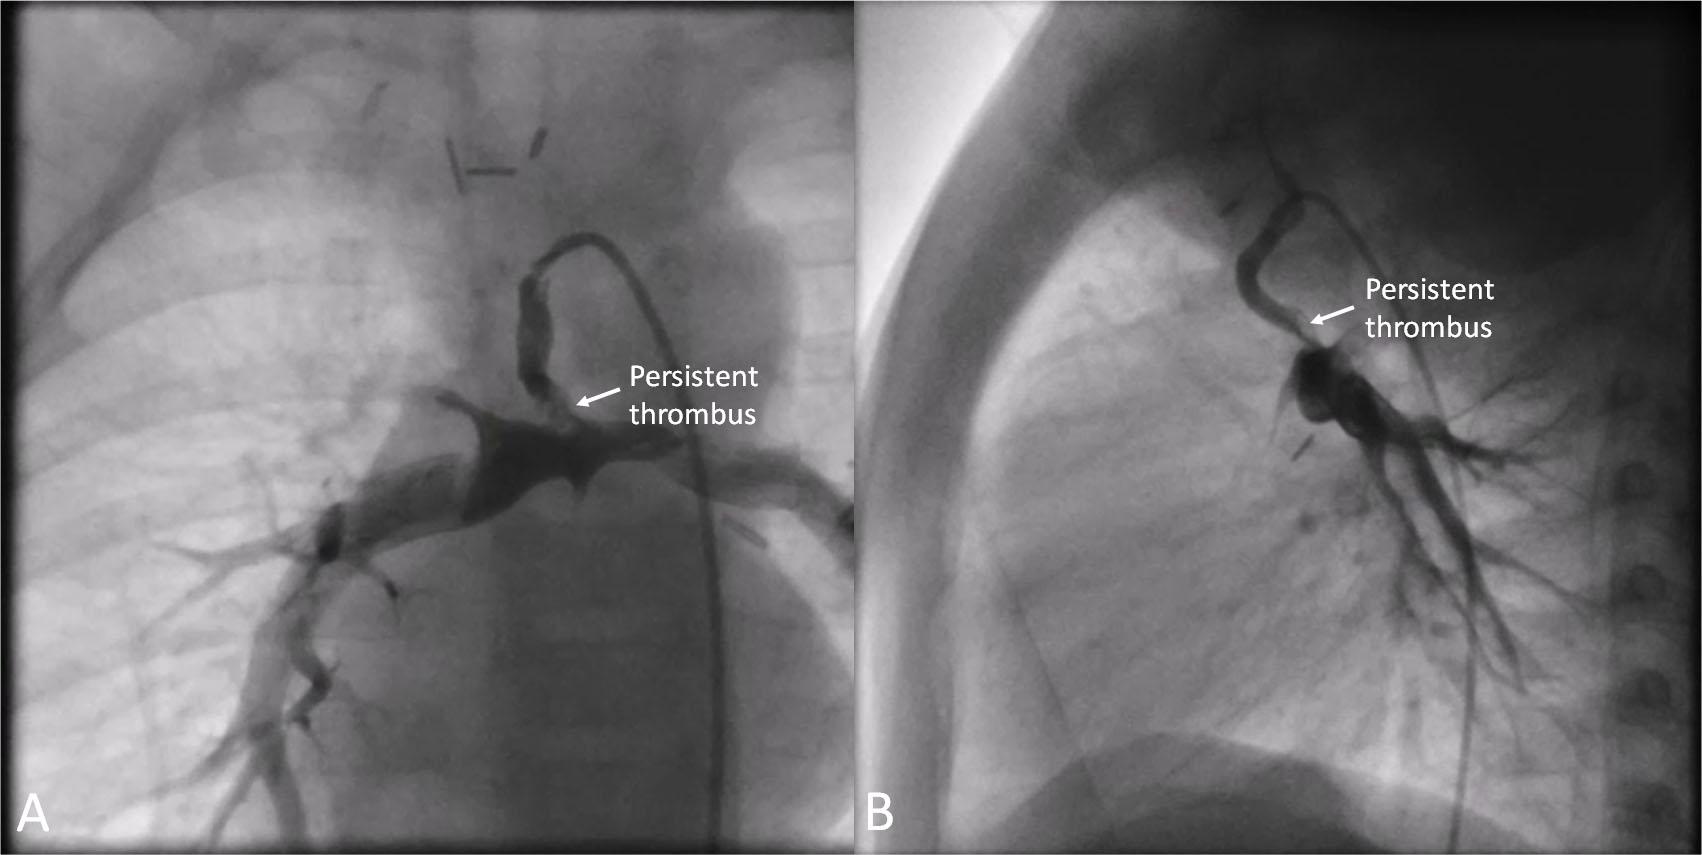

Figure 3